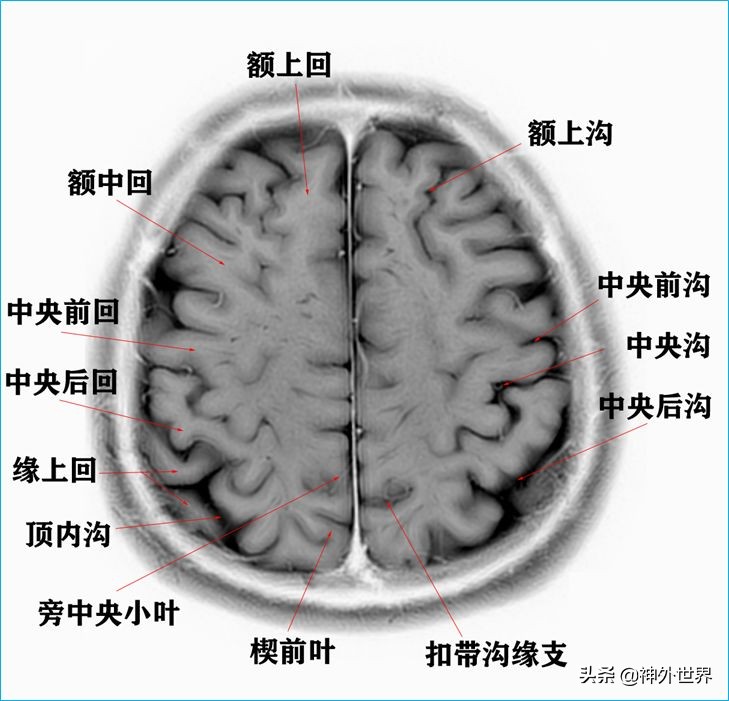

1、水平位连续切片

以下图片均来自我院3.0T核磁共振的T2WI反相图。标注均为我自己完成,水平有限,难免有误,还望各位老师多多指正。谢谢。